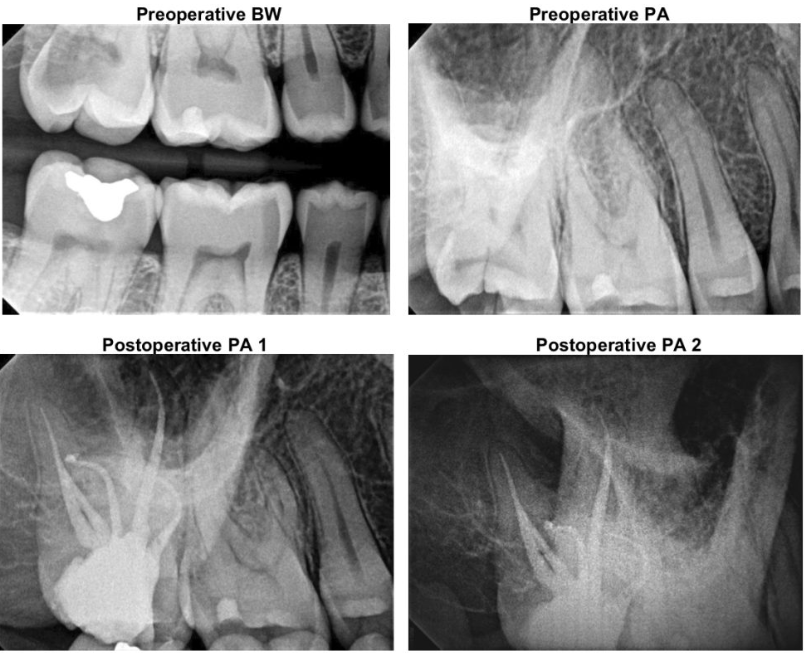

Root Canal Treatment of Tooth #18:

Diagnosis: #18 Pulp Necrosis with Symptomatic Apical Periodontitis

Tooth was occluded to the upper denture. The patient reported pain and was not able to chew on the left side. Percussion and biting tests suggested that the pain was from the tooth #18. Tooth #18 is a necrotic tooth with secondary caries exposing the pulp. A periapical bone damage (i.e. periapical radiolucent lesion) was also noticed around the M and D roots of the tooth #18.

The pain resolved after the root canal treatment was completed on the tooth #18. At 1 year recall, the tooth remained asymptomatic with the healing of periapical bone.